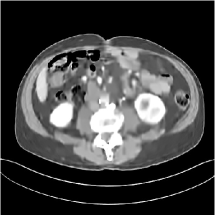

III.C. Low-dose Experiments with Mayo Clinic Data

First, we study transform training based on Mayo Clinic data. As shown in Fig. 6, seven slices obtained at regular dose from three patients are used for transform learning. The number of pixels . Similar to the phantom experiments, overlapping patches are extracted with a patch stride. The number of overall training patches is about . We set for ST, , , for MARS2, , , , , for MARS3, , , , , , , , , for MARS5, , , , , , , , , , , , , for MARS7. The iteration number in Algorithm 1. Fig. 7 illustrates the learned transforms obtained with Mayo Clinic data. Different from the XCAT phantom case, these transforms up to MARS5 display more complex features and structures. The rich features of the MARS models better sparsify the training images over layers compared to the single-layer model (ST).

III.C.2. Simulation Framework, Reconstruction Results, and Comparisons

The synthesized low-dose clinical measurements are simulated from regular-dose images at a resolution of mm with a fan-beam CT geometry corresponding to a monoenergetic source at incident photon intensity . The sinograms are of size . The width of each detector column is mm, the source to detector distance is mm, and the source to rotation center distance is mm. We reconstruct images of size with the pixel size being mm mm.

We conducted experiments on one test slice used for parameter tuning (L067-slice 120) and four independent test slices (L109-slice 90, L192-slice90, L333-slice140, L506-slice 100) of the Mayo Clinic data. For PWLS-EP, we ran iterations using relaxed OS-LALM and set regularization parameter . We used the same as the phantom experiments for Algorithm 2. The process of selecting a general set of reconstruction parameters () for the Mayo Clinic test slices is identical to that for the XCAT phantom in Section III.B.2. The selected regularization parameter and the parameters that control the sparsity of the coefficient maps are for ST, , , , , for MARS2, , , , , , , for MARS3, , , , , , , , , , , for MARS5, and , , , , , , , , , , , , , , for MARS7, respectively.

Figs. 8, 9, 10, and 11 show the reconstructions of the four independent slices using the FBP, PWLS-EP, PWLS-ST, PWLS-MARS2, PWLS-MARS3, PWLS-MARS5, and PWLS-MARS7 schemes, respectively. Additional Mayo Clinic experimental results of the parameter tuning case (Fig. 15) are shown in the supplementary document. Table 1 lists the RMSE and SSIM values of reconstructions of the four independent test slices, with the best values bolded. Generally, the five and seven layer models provided the best RMSE and SSIM values. They outperform the single-layer model by HU in RMSE on average. However, the MARS5 and MARS7 models perform similarly. In order to strengthen the benefits of the multi-layer model, Table 2 lists the RMSE of the reconstructions in four different ROIs (shown in the reference of Fig. 11) with seven methods for slice 100 of patient L506. By observing the reconstructed images, we see that although the ST model achieves a cleaner reconstruction result than FBP and PWLS-EP, it still sacrifices some sharpness of the central region and suffers from loss of details. The deeper models have a somewhat more positive effect in terms of maintaining subtle features, which is clearly more essential to clinical diagnosis. Furthermore, as we will discuss later, after considerable parameter tuning, we found that the information contained in residual maps is gradually decreased with the number of layers, eventually vanishing at some layer, which suggests that very deep unsupervised models might not offer significantly better image quality.